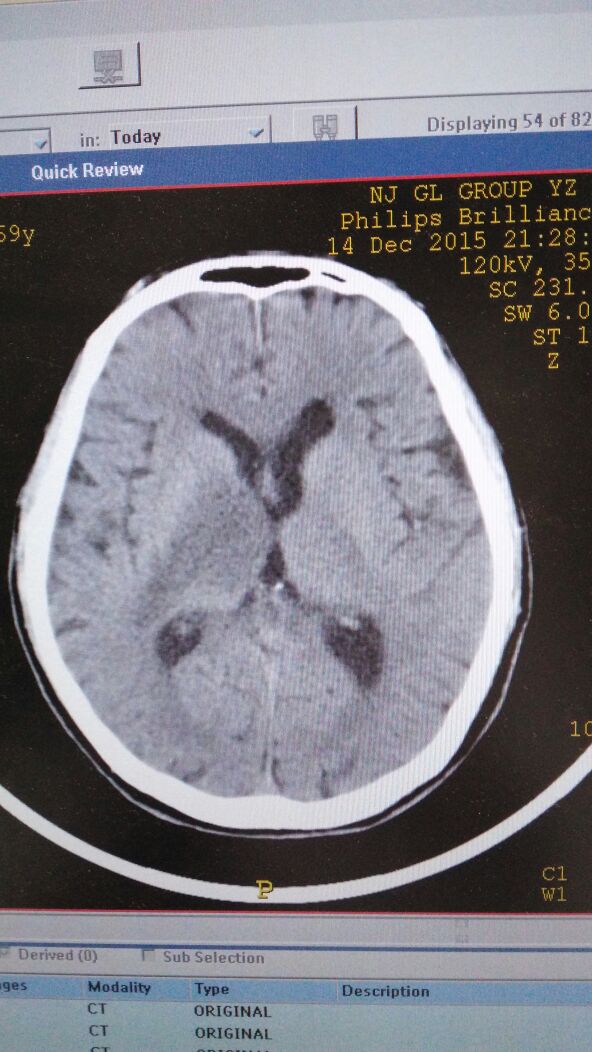

颅CT示双侧大脑皮质广泛低密度,以双侧颞叶明显,未见明显的占位效应。根据上述病史及头颅CT所见,非特异性脑炎不除外。为进一步明确诊断,行头颅MRI检查:双侧颞叶片状长T1及右侧额叶斑片状略长T1信号,T2WI示上述部位明显长T2信号,增强后脑实质内可见多个团块状或环状强化病灶(见图1、图2)。

拟诊断脑转移癌。进一步行肺部CT检查,提示右肺中心型肺癌伴纵隔淋巴结转移,确诊为肺癌脑转移。